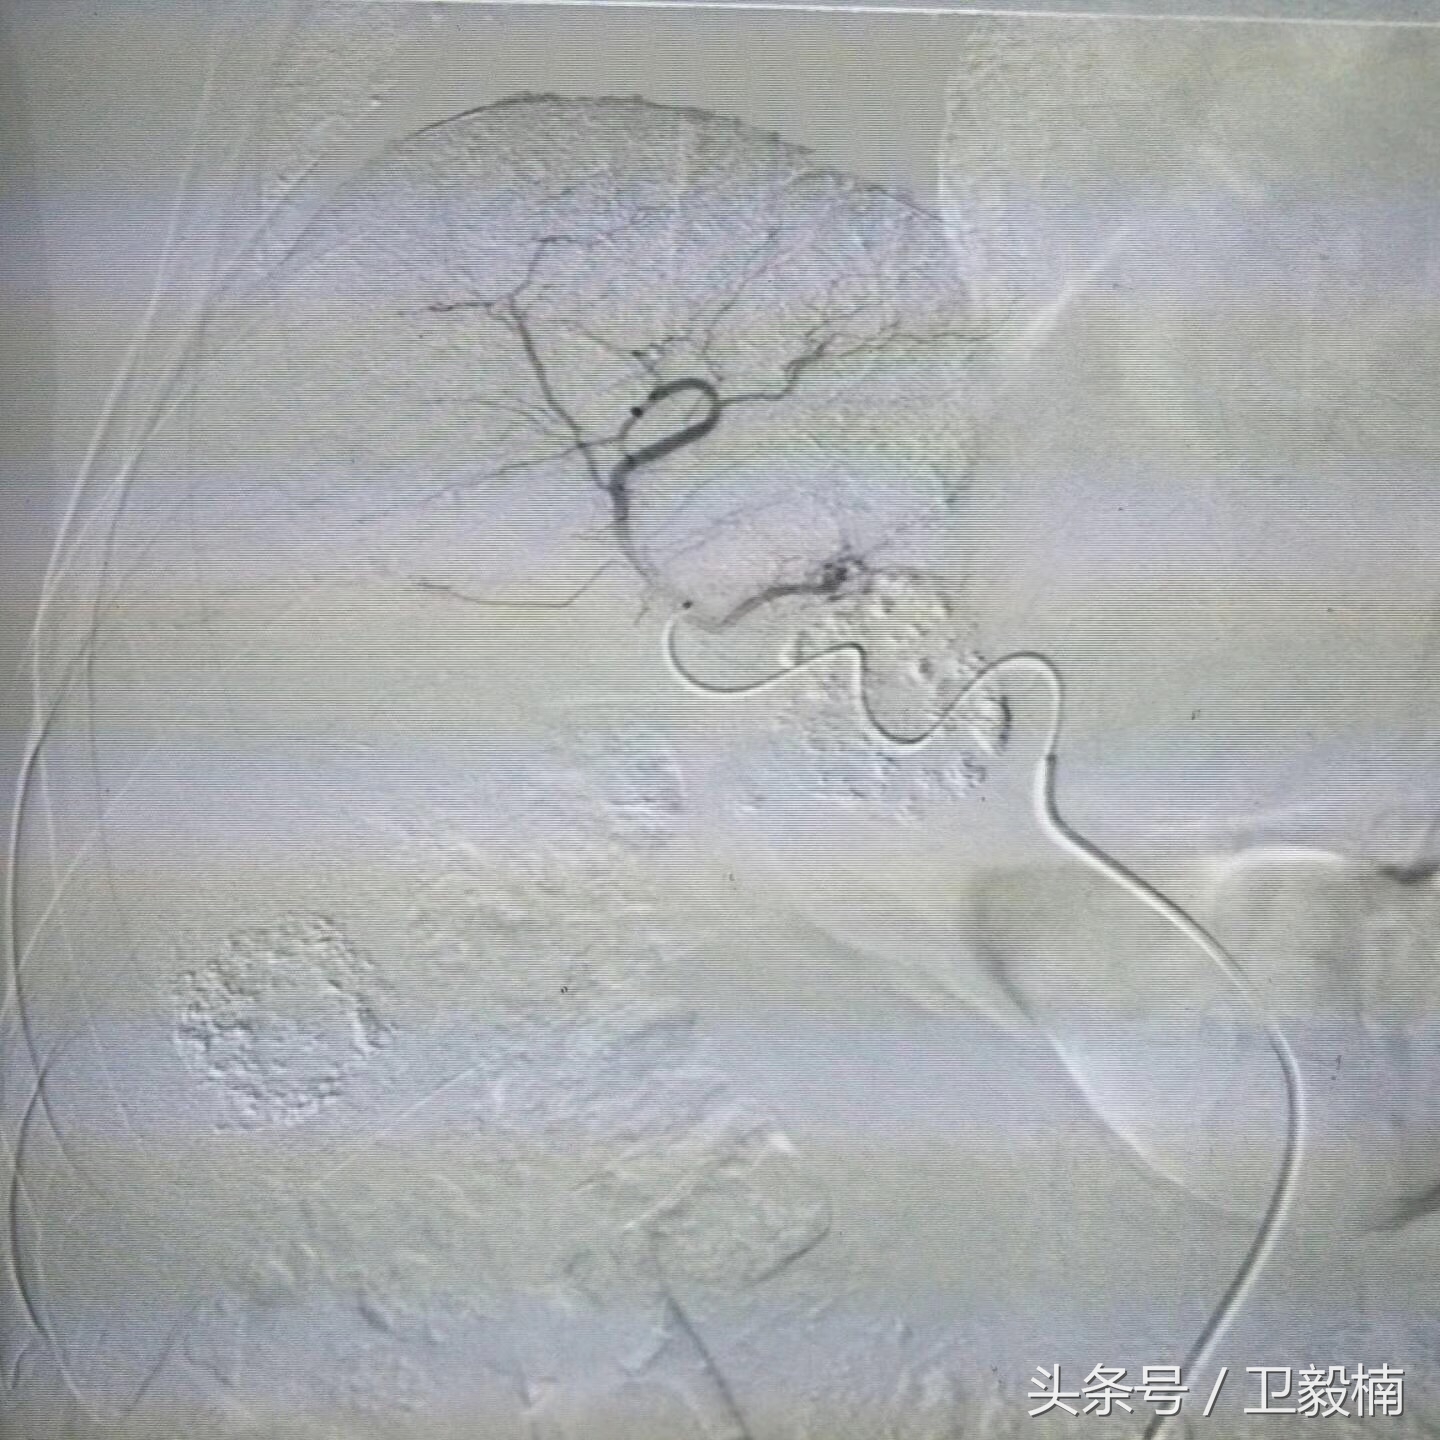

我院综合介入治疗中心 近期对一肝内多发患者行介入治疗,术后患者4天出院,伤口仅有一个针眼大小。

栓塞前